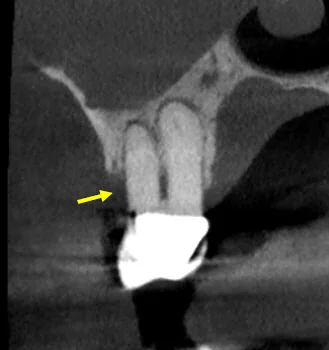

What the CBCT Showed

The 3D imaging revealed several findings that didn't fit a routine endo-perio presentation: calcification within the canal, furcation involvement, and — most concerning — irregular bone borders with cortical plate erosion. The borders weren't smooth the way you'd expect with a standard infection or cyst. They were ragged and ill-defined, which in rare cases can indicate malignancy.

Our working differential included a combined endo-perio lesion, a vertical root fracture, and — given the irregular CBCT borders — possible maxillary sinus carcinoma. Sinus malignancies account for less than 0.2% of maxillary sinus pathologies, but the cortical plate erosion pattern on this CBCT was not something we could ignore.

• Irregular CBCT Borders Are a Red Flag: Smooth, well-defined radiolucencies suggest infection or cysts. Ragged, ill-defined borders with cortical plate erosion should raise suspicion for malignancy and warrant further investigation.

• 2D Radiographs Can Be Deceiving: The periapical radiograph in this case appeared relatively normal. Without CBCT, the irregular bone destruction pattern would have been missed entirely.